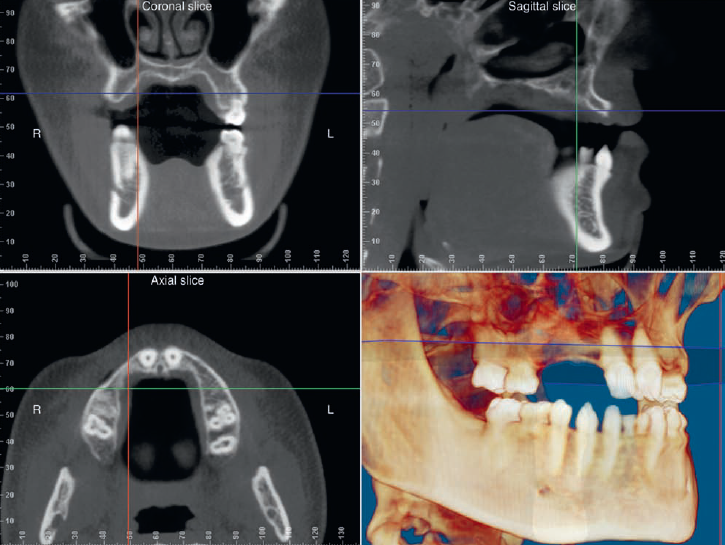

فایل‌های داده‌ی تصویری حاصل از سی‌تی (CT) و سی‌بی‌سی‌تی (CBCT) را می‌توان با نرم‌افزارهای شبیه‌سازی مخصوص روی رایانه بازسازی و مشاهده کرد. این قابلیت موجب افزایش دقت در روند تشخیص و برنامه‌ریزی درمان ایمپلنت می‌شود؛ زیرا اندازه‌گیری‌ها و ابعاد به‌صورت کاملاً واقعی و سه‌بعدی قابل بررسی هستند.

در این نرم‌افزارها می‌توان ساختارهای آناتومیک حیاتی را در تمامی محورهای سه‌گانه مشاهده نمود: در محورهای فوقانی–تحتانی (Superior–Inferior)، قدامی–خلفی (Anterior–Posterior) و دهانی–زبانی (Buccal–Lingual). این ویژگی امکان تعیین دقیق موقعیت‌های حیاتی را فراهم کرده و در نتیجه هنگام تصمیم‌گیری درخصوص امکان و محل دقیق قراردهی ایمپلنت، اطلاعات حیاتی و قابل اعتماد در اختیار دندان‌پزشک قرار می‌دهد.

شکل III‑2 — اسکن CBCT سه‌بعدی فک بالا

شکل III‑2. اسکن سی‌بی‌سی‌تی که امکان مشاهده‌ی چندین ساختار را در سه بُعد فراهم می‌سازد.

بالا چپ: برش کرونال از ناحیه بی‌دندان خلفی با نمایش سینوس ماگزیلاری و استخوان ستیغ آلوئولار.

بالا راست: برش عرضی از ناحیه قدامی فک بالا.

پایین چپ: نمای آکسیال که کمبود ستیغ قدامی را نشان می‌دهد.

پایین راست: بازسازی سه‌بعدی از ساختار استخوان فک.